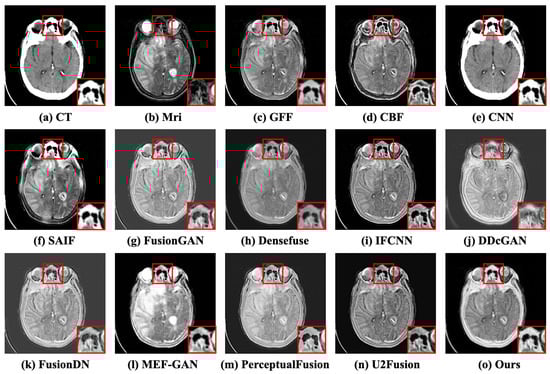

Case 1: Acute stroke presenting as speech arrest. The experimental data were obtained from a patient who was a 63-year-old right-handed male with a history of Micronase-treated adult-onset diabetes mellitus and arterial hypertension ([Online]. Available: http://www.med.harvard.edu/aanlib/cases/case2/case.html, accessed on 15 May 2023). The subjective comparison results of the first case are depicted in Figure 7. The CT image is commonly negative during the acute period of stroke, and the MRI image reveals acute cerebral infarction involving the left pre-central gyrus. Preferably, the fused image retains the bone part from CT and the textural information from MRI. Although the traditional methods (e.g., GFF [10], CBF [11], and SAIF [12]) perform well in persevering soft tissues from images, they exhibit poor results in maintaining the illumination intensity of images. The white contour in the CT image shows the skull, but the fusion of GFF and CBF results in the loss of a majority of the skull information. The CNN-based methods (e.g., CNN [13], IFCNN [15], FusionDN [16], and U2Fusion [17]) and GAN-based methods (e.g., DDcGAN [21] and PerceptualFusion [22]) have lower contrast in the skull part. The details of brain tissue are sufficiently clear, except for FusionGAN [35] and MEF-GAN [36]. Densefuse [14] and PerceptualFusion [22] lack some tissue information in the boundary between encephalic tissue and the skull in the red box, close-up. DDcGAN [21] and CFGAN retain the skeletal information of CT images more than other competitors. DDcGAN [21], FusionDN [16], and CFGAN have high contrast, as well as preserving soft tissue information. The objective results are depicted in Table 1. It illustrates that the proposed CFGAN performs best in the other four objective indicators except for the CC indicator, in which the CFGAN ranks fourth place.

Figure 7.

The subjective comparison results of the first case. (a,b) represent the CT and MRI images. (c–n) denote the fused results of the competitors. (o) is the result of CFGAN. In this and following figures, at the bottom right of each subfigure, we show the highlighted image in red box.

Case 2: Acute stroke presenting as right body weakness. This case is from a 45-year-old female with a sudden onset of right body weakness and trouble speaking ([Online]. Available: http://www.med.harvard.edu/aanlib/cases/case20/case.html, accessed on 15 May 2023). The subjective comparison results of the second case are depicted in Figure 8. These methods (e.g., GFF [10], SAIF [12], Densefuse [14], and IFCNN [15]) preserve some tissue texture information, but the fused images have lower contrast, resulting in missing cephalometric information. The comparison between CNN [13] and FusionGAN [35] has higher contrast, but the edges are blurred, and some information about brain tissue is lost. The MEF-GAN [36], U2Fusion [17], and PerceptualFusion [22] are unable to attain distinct textures or boundaries. The superior colliculus of the fused results in the red box (e.g., DDcGAN [21], FusionDN [16], and CFGAN) has higher brightness and richer details, but the bone information of DDcGAN [21] lacks details, including edges and texture. Our proposed method can reserve more significant information, particularly gradient information, contrast, boundary, and textural details. The objective comparison results are denoted in Table 2. It illustrates that the proposed CFGAN ranks first in SD, PSNR, SSIM, and MI. For the CC and VIF indicators, the CFGAN ranks third and second, respectively.

Figure 8.

The subjective comparison results of the second case. (a,b) represent the CT and MRI images. (c–n) denote the fused results of the competitors. (o) is the result of CFGAN.

Case 3: Multiple infarctions. The third case is a 55-year-old male who suffered multiple refractory focal seizures in the setting of pulmonary empyema ([Online]. Available: http://www.med.harvard.edu/aanlib/cases/case34/case.html, accessed on 15 May 2023). The fused results of the subjective comparison for the third case are illustrated in Figure 9. The source MRI has more clarity and more tissue detail than the CT image, and it makes sense for both of the above pieces of information to be retained in the fused image. Nevertheless, these methods (e.g., GFF [10], CBF [11], and FusionGAN [35]) have weak visual contrast. There are distortions in the contours of images (e.g., SAIF [12], DDcGAN [21], IFCNN [15], and MEF-GAN [36]). In general, SAIF [12], DDcGAN [21], and CFGAN achieve superior perceived quality. Viewing the atrium in the red box, we can observe that CBF [11], SAIF [12], IFCNN [15], DDcGAN [21], U2Fusion [17], and CFGAN reserve more texture details. The six objective evaluation indicators are presented in Table 3. The proposed method CFGAN is proved to show better performance compared to the other twelve methods.

Figure 9.

The subjective comparison results of the third case. (a,b) represent the CT and MRI images. (c–n) denote the fused results of the competitors. (o) is the result of CFGAN.